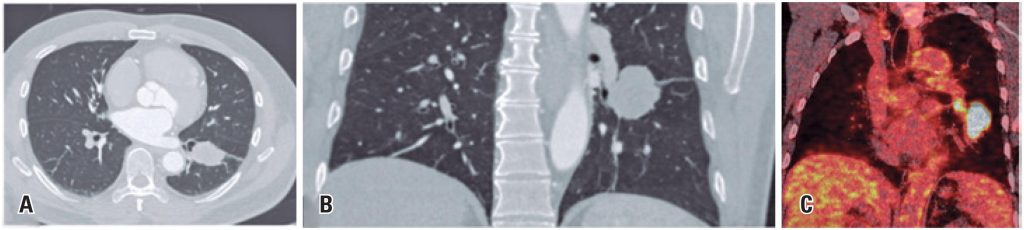

Lung cancer represents the most commonly diagnosed neoplasm and the leading cause of cancer-related death worldwide, with majority of the patients being histologically categorized as non-small cell lung cancer. We present the case of a 54-year-old male patient, with a smoking history of 30 pack-years and no other comorbidities, with a pulmonary mass in the left lower lobe () incidentally revealed by computed tomography (CT). After pathological confirmation of adenocarcinoma with hilar lymph node metastasis (cT2b pN1 M0, EIIB), the patient underwent neoadjuvant therapy with carboplatin AUC6, pemetrexed 500mg/m2, and nivolumab 360mg (three cycles with a three-week interval), with a planned curative lower left lobectomy and lymph node dissection. Positron emission tomography (PET)-CT images following neoadjuvant treatment revealed increased size and heterogeneous enhancement of bilateral mediastinal and hilar lymph nodes (). Concerns about disease progression were raised, but histological analysis indicated a granulomatous reaction consistent with a sarcoid-like reaction (SLR), with post-neoadjuvant pathological staging of ypT1c ypN0.